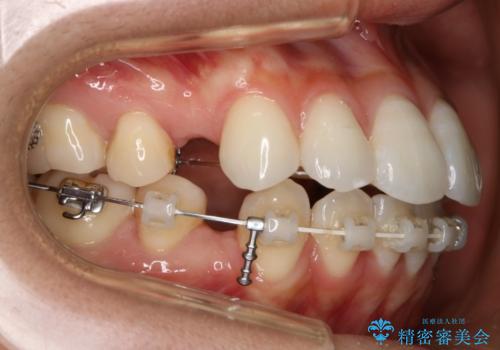

- ワイヤー(片顎舌側装置)

- 治療計画

ハーフリンガル装置

ハーフリンガルとは上顎を裏側、下顎を表側のワイヤー装置で治療する場合をいいます。

フルリンガル(上下とも裏側)で治療するよりも費用が抑えられ、治療期間も伸びにくい傾向にあります。また、下顎の舌側に装置がないおかげで口内炎や発音障害もフルリンガルに比べて少ないとされています。